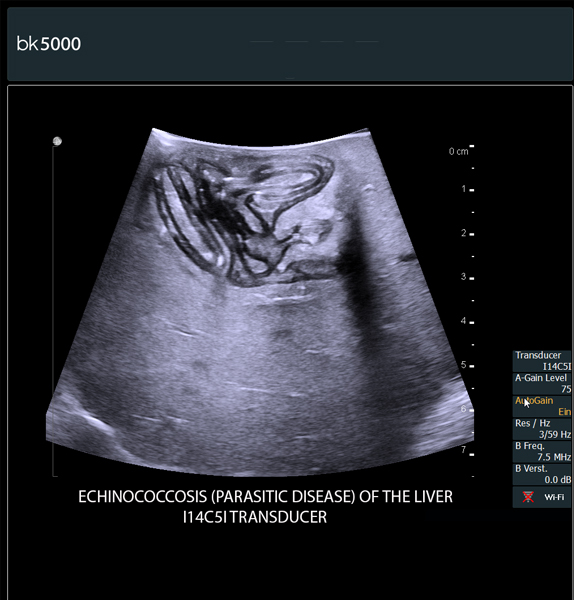

The bk5000 surgical system provides the highest quality images that allow you to clearly see the margins of a lesion and to determine the best course of action. Using advanced graphics processing technology, this powerful system provides immediate, auto-optimized images that allow you to see the information you need, faster.